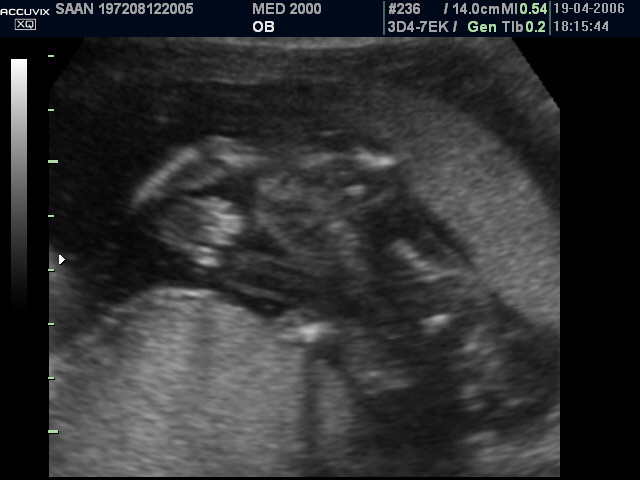

Le anomalie scheletriche più comuni sono le anomalie del raggio radiale: ipoplasia o aplasia del radio, pollice a tre falangi, mano torta, a volte assenza del pollice.